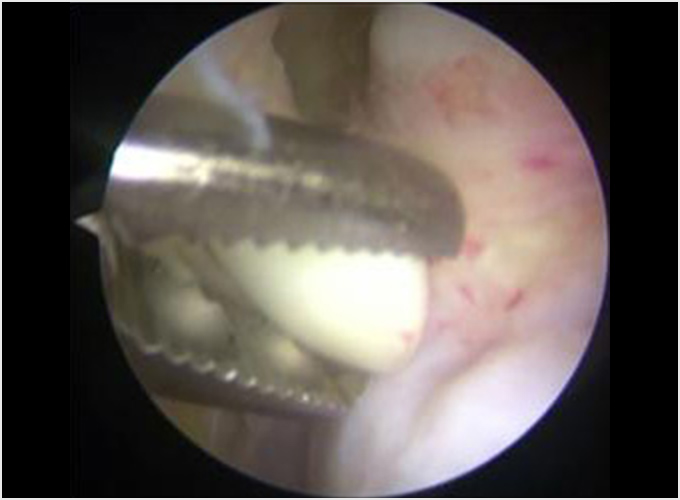

野球肘で最も重症になる障がいの1つです。ひどくなると関節軟骨の一部がはがれて関節ネズミとなったり、肘が変形して動きが悪くなったりします。初期に発見されれば投球禁止で治り、手術はしなくてもすむ場合が多いのですが、末期になると手術が必要となり、手術をしても肘の動きの制限や変形が残ってしまうこともあります。10歳前後で発症することが多いのですが、初期には自覚症状がないことが多く、13-17歳ごろにグラグラになった軟骨がはがれて痛みが出て初めて医療機関を受診されることもよくあります。 手術となった場合には骨の成長の度合い、病変の進行具合、病変の大きさなどにより手術方法が変わります。軟骨が安定している場合には軟骨を固定する手術を行う場合が多いです。軟骨がはがれている場合、病変が小さければ関節鏡を用いてはがれた、あるははがれかけている軟骨を摘出します(図4a)。病変の直径が1㎝以上であれば切開手術で膝の軟骨を病変部に移植します(図4b)。 最近全国各地で少年野球検診が行われるようになりましたが、一番の目的は離断性骨軟骨炎を早期に発見し、重症になる前に治療を行うことなのです。平成28年から多くの医師、理学療法士の協力により名古屋でも行われるようになりました。私も検診に参加し、エコーでのチェックを担当しました。およそ100人に1-2人の割合で発見されました。